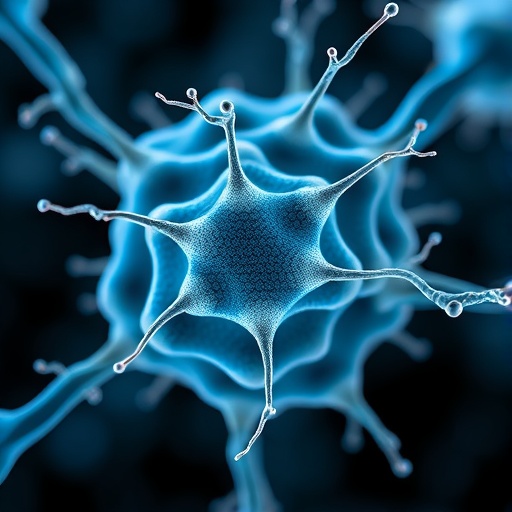

In an era where regenerative medicine and bioelectronics are converging to push the frontiers of healing, a groundbreaking study published in npj Flexible Electronics in 2026 has revealed a transformative approach to nerve repair. The research, led by Wang, E., Huang, J., Shan, Y., and colleagues, introduces bioabsorbable silicon-magnesium (Si-Mg) galvanic cells integrated within flexible scaffolds. These innovative structures deliver symbiotic electrical stimulation directly to damaged nerves, accelerating and enhancing the regenerative process. The implications of this development could redefine therapeutic strategies for nerve injuries, offering a new beacon of hope for patients suffering from chronic and debilitating nerve damage.

At its core, nerve regeneration faces significant challenges due to the slow and often incomplete recovery of neural function after injury. Conventional treatments rely heavily on physical therapies or complicated surgical grafts, neither of which guarantees optimal nerve regrowth or functional restoration. Electrical stimulation has been recognized for decades as a potential enhancer of nerve healing, but the methods of delivering such stimulation have been constrained by rigid, non-biodegradable implants that can provoke immune responses or require invasive removal procedures. Enter the bioabsorbable Si-Mg galvanic cell, whose ingenious design circumvents these limitations by marrying biocompatibility and electrical functionality within a flexible, dissolvable platform.

What makes the Si-Mg galvanic cell exceptional is its exploitation of galvanic corrosion between silicon and magnesium materials. When immersed in physiological fluids, the dissimilar metals set up an electrochemical reaction that produces a sustained electrical current, perfectly tailored for stimulating nerve tissues. Unlike traditional batteries or external electrical devices, the galvanic cell harnesses the body’s own ionic environment to fuel its operation, ensuring a consistent, low-intensity stimulation that encourages axon elongation and synaptic reconnection without detrimental side effects. The ability of this system to function autonomously marks a considerable leap toward truly implantable bioelectronics.

Flexibility in the scaffold plays an equally vital role in the success of this nerve regeneration strategy. Human nerves possess intricate geometries and movements, making it crucial that any implanted device conforms to the native tissue architecture to avoid mechanical mismatch and subsequent inflammation or scarring. The researchers engineered a scaffold that integrates the Si-Mg galvanic cells into a pliable substrate capable of bending and stretching with the nerve’s natural motion. This biomechanical harmony not only enhances patient comfort but also improves electrical contact and interface stability, thereby optimizing therapeutic outcomes.

One of the most fascinating aspects of this work lies in the concept of symbiotic electrical stimulation. Unlike mere external electrical pulses imposed upon the nerve, the electrical output from the galvanic cells is intricately synchronized with the biological milieu. This symbiosis allows the electrical current to modulate cellular processes such as ion channel activity, growth factor expression, and cytoskeletal reorganization in neurons and supporting glial cells. The resulting concert of biochemical and biophysical cues fosters an environment highly conducive to nerve repair, thereby surpassing the efficacy of traditional stimulation paradigms.